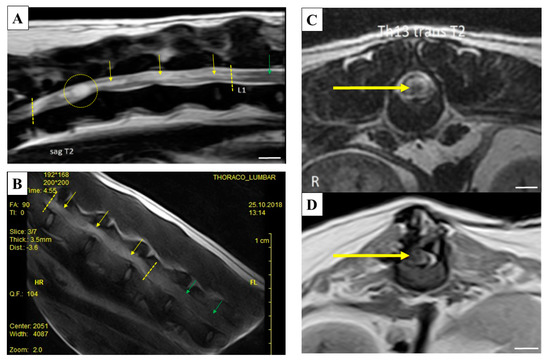

4.2. Dogs Suffering from SCI

| Breed | Dogs Name | Lesion Site | Age | Gender | Body Weight |

|---|---|---|---|---|---|

| Shi-tzu | Zuzi (Dog Z) | T11-L1 | 4 | Female | 5.4 kg |

| German Shepherd | Bak (Dog B) | T13-L2 | 6 | Male | 24 kg |

| Yorkshire Terrier | Max (Dog M) | T11-T12 | 5 | Male | 4 kg |

| Bichon | Tia (Dog T) | T13-L1 | 4 | Female | 6.4 kg |